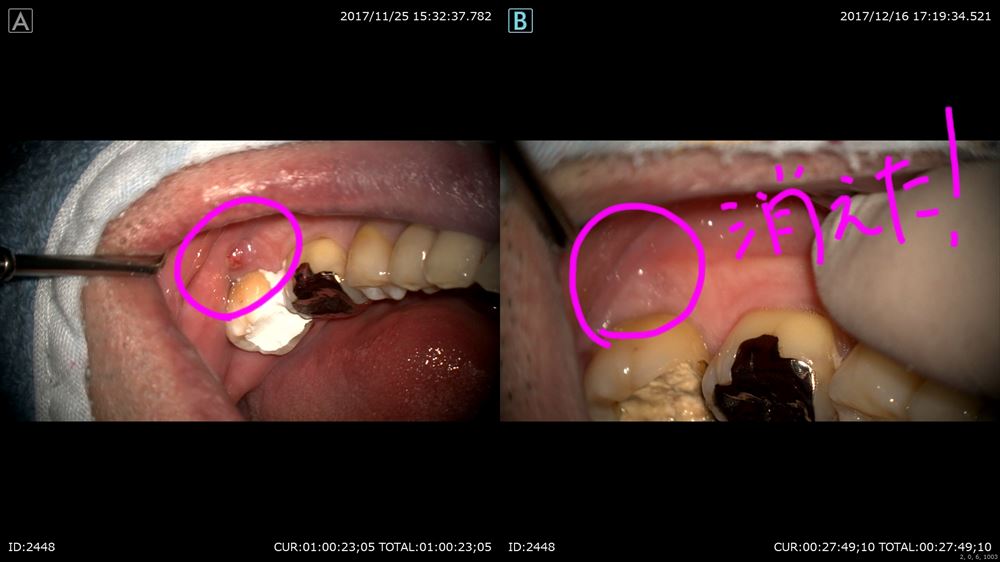

以前から腫れが引かないと悩まれていた方。とても心配していました。

左下が腫れていました。

根管を清潔にする事が出来て

結果が出てきました。

術前左、術後右

次回根管充填です。